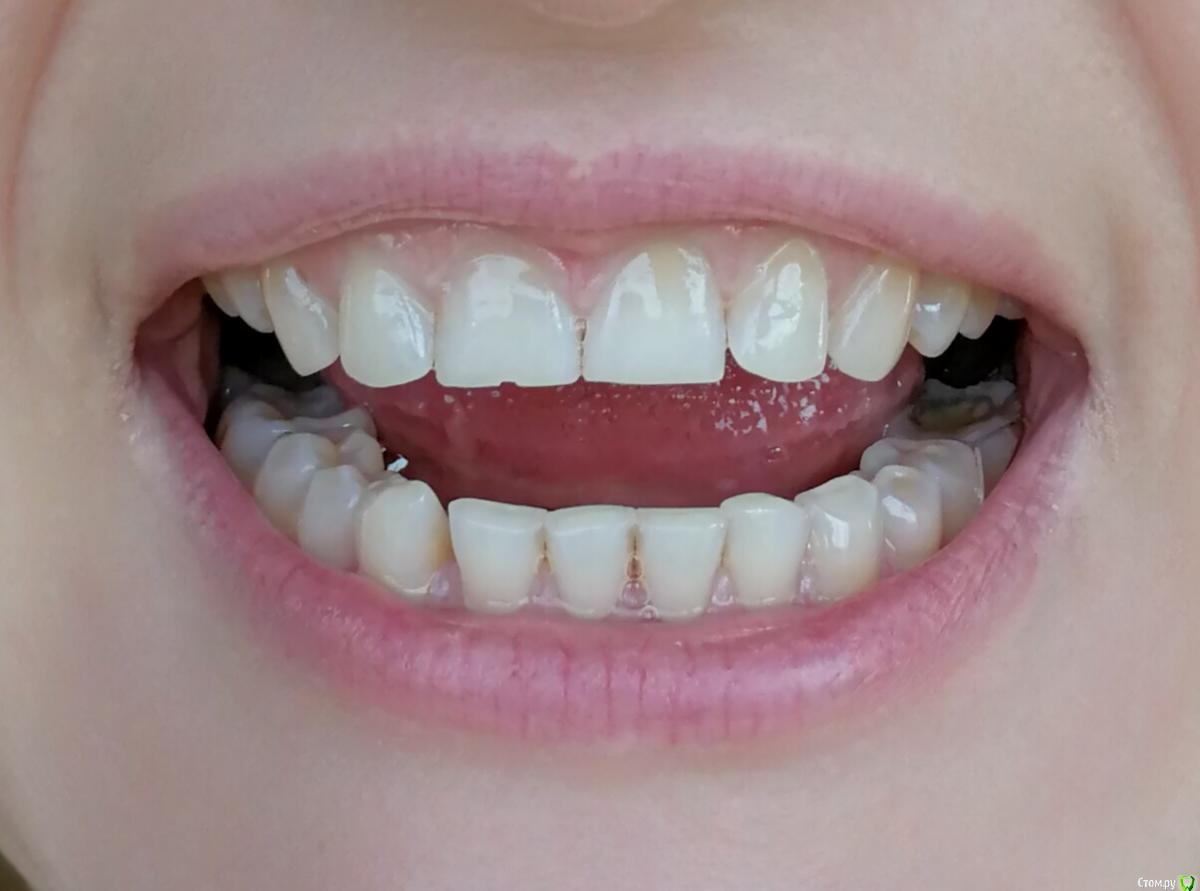

Ольга2000 Опубликовано 27 октября, 2019 Поделиться Опубликовано 27 октября, 2019 Здравствуйте. Мне 37 лет, ничего не беспокоит, нет повышенной чувствительности, кровоточивости. Мне кажется, что такие зубы у меня были последних лет 10, т.е. каких то изменений я не замечала.Делая последний раз гигиену ротовой полости врач сказала, что ей не нравится мой прикус. Через некоторое время я открывала зубами лекарство (понимаю, что так нельзя) и откололся кусочек переднего зуба. Это и подтолкнуло к записи к врачу.Первый врач осмотрел, сделал фотографии и сказал, что надо поднимать прикус с помощью пломб, пломбировать оголённые шейки зубов и ещё на отбеливание записал.Вчера была на приёме у ортодонта. Сделал снимок, сказал что с прикусом ничего не надо делать, посоветовал проконсультироваться с пародонтологом, т.к. поднимается кость. Я не знаю что мне делать. У меня следующие вопросы: 1. Надо ли поднимать прикус?2. Надо ли пломбировать оголение шеек зубов?3. На 11 и 21 зубах бороздки. Что с ними делать?4. Может капу на ночь сделать, чтобы зубы не стирались?5.И вообще что мне надо делать в обязательном порядке? И в необязательном тоже. Спасибо за ответы. Ссылка на комментарий

krokomot Опубликовано 27 октября, 2019 Поделиться Опубликовано 27 октября, 2019 По вашим фотографиям не возможно сказать нужно ли вам поднимать прикус, скорее всего да, слевой стороны у вас стираемость зубов, зубы попадают бугор на бугор, есть смещение центральной линии. также с левой стороны 6й зуб визуально не в очень хорошем состоянии. нужно ли вам что то делать? вы должны решить сами, зубы слева на буграх сточены до дентина, то есть эмаль уже полностью стерта далее с течением времени зубы начнут изнашиваться всё быстрее и быстрее. наличие полосок на нижних зубах можно не пломбировать, а скорректировать чистку зубов перейдя на выметающие движения , а не горизонтальные. если вы хотите еще 37 лет прожит со своими собственными зубами и не испытывать проблем, то нужно пройти ортодонтическое лечение и восстановить анатомию стертых зубов керамикой. Это остановит стираемость, а можете это сделать через 10 лет, но объем вмешательства возрастет кратно... 1 Ссылка на комментарий